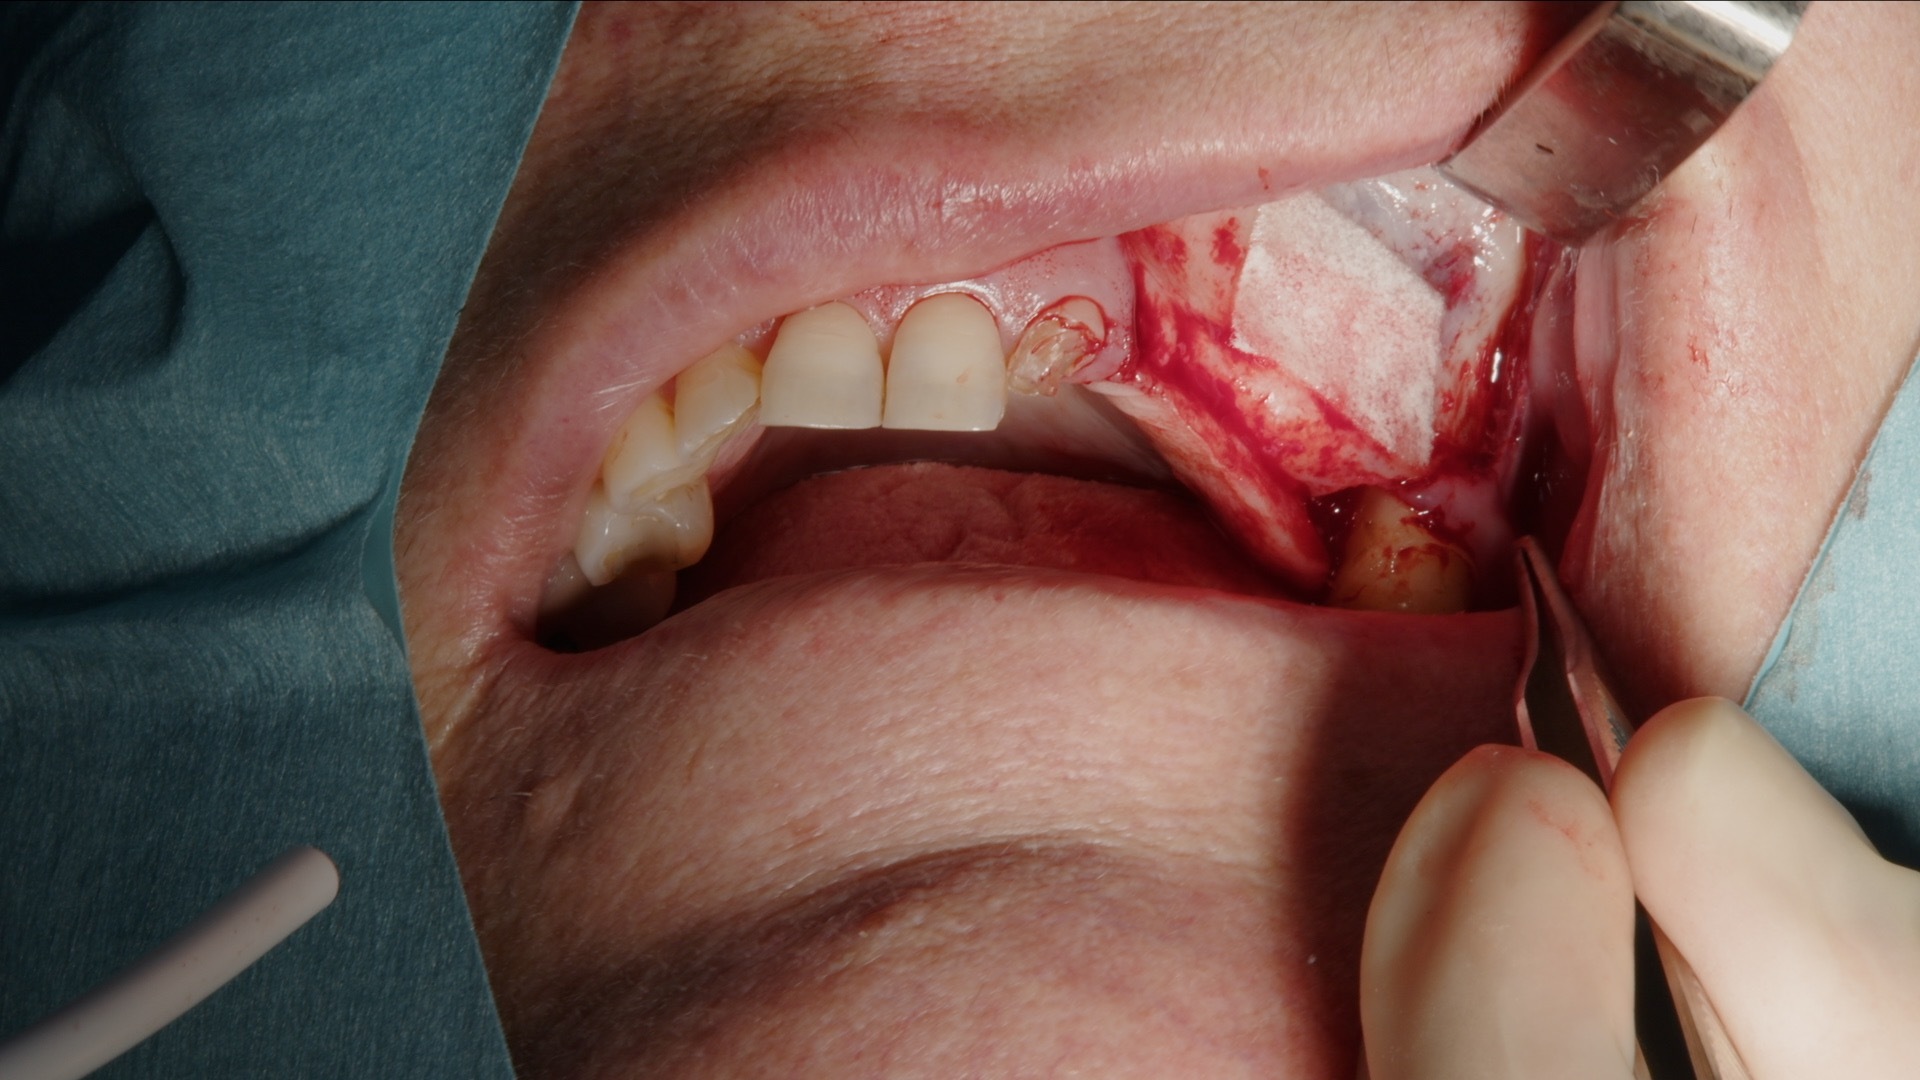

1. Incision och lambåpreparation inför skapande av lateralt fönster.

2. Preparering av lateralt fönster med Acteon Piezo Cube och diamantspets.